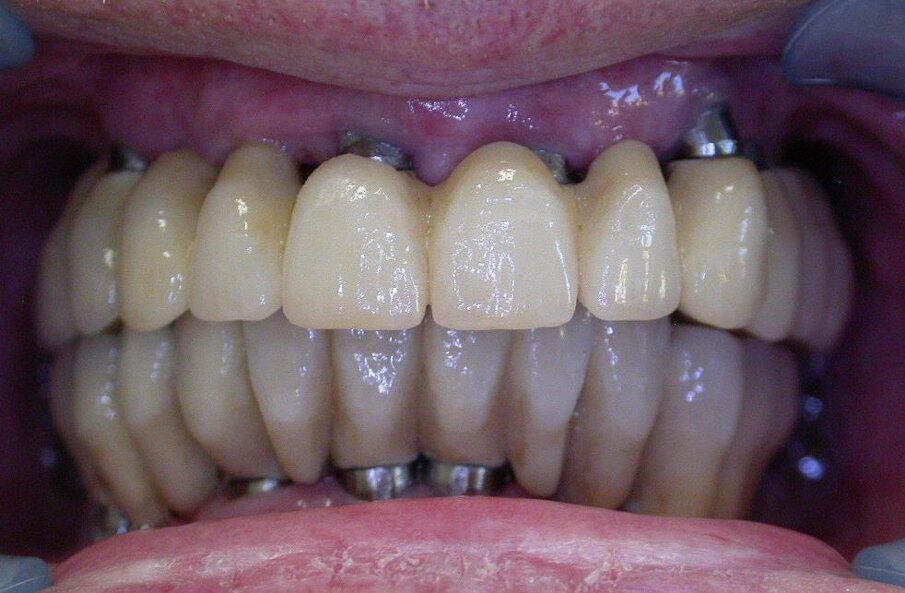

Un signore settantenne si rivolge a un odontoiatra per un ripristino protesico superiore. Ha già una vecchia protesi, ma si muove e gli sembra soprattutto brutta e vetusta, anche se mangia bene (Fig. 1). Il professionista propone due Toronto, una superiore e una inferiore, con denti in ceramica su impianti a carico immediato, previa estrazione di tutti i denti residui. Lavoro da realizzare in 4/6 mesi. Pagamento ad avanzamento lavori e saldo alla fine a “protesi ben allocata senza problemi” (preventivo € 20.000,00, pagati € 16.000,00). Promette soprattutto estetica, “niente metallo visibile, tutta ceramica”.

Inoltre, la protesi traumatizza con le parti metalliche i tessuti molli e la lingua, le corone sono inclinate in senso vestibolare e non occludono alla perfezione. L’overjet è ampio ed è presente un morso aperto anteriore, con trauma sui posteriori. Si vedono i colletti metallici degli impianti, metallo compare negli spazi interprossimali (corone ed impianti non sono in linea)(Figg. 2-4).